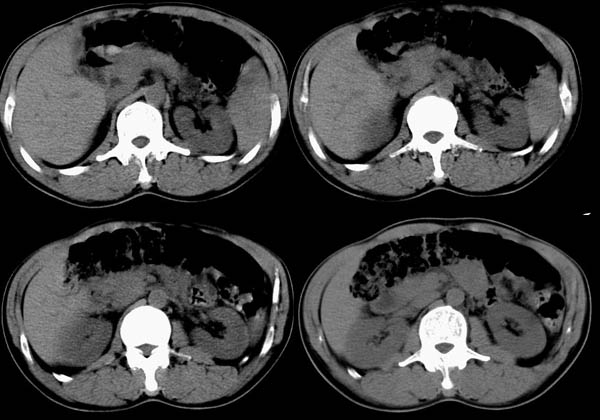

m50y以腹疼、腹胀2小时就诊。腹透肠胀气较明显,余无明显异常。做ct时腹疼已明显缓解;病人否认外伤史,否认血液病变、否认肝炎史。建议第二天做ct增强,病人第二天放弃了增强。脾脏区较高密度影ct值为60hu,正常脾脏ct值为45hu(窗宽:150,窗位:56)。

ct表现:脾脏内见较高密度影ct值为60hu,正常脾脏ct值为45hu(窗宽:150,窗位:56)。 边界清晰,周围见略低密度影

脾脏实质内高密度病变,ct值为60hu,边界清晰,无明显外伤病史,腹痛、腹胀2小时就诊,首先考虑脾脏血管瘤破裂出血。